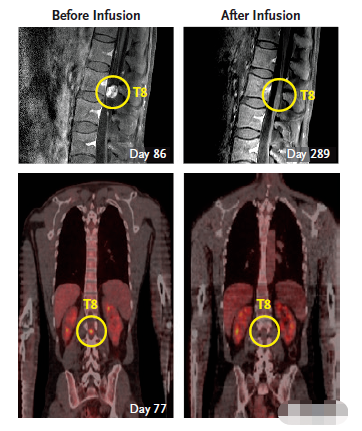

3次治疗之后,Grady脑中的全部肿瘤都发生了急剧的收缩。在10次治疗后(3周后),Richard Grady拿到了他的脑部扫描结果,他脑部的5个肿瘤全部消除了!这真是个奇迹,就连医生都很惊喜,他全部的肿瘤都在消退。

二轮CAR-T疗法结束后,Richard Grady脊索内肿瘤出现剧烈萎缩